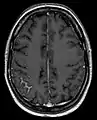

Screening involves an MRI scan to identify and diagnose tumors in the subarachnoid region of the brain. MRI can make a diagnosis even without an analysis of the cerebrospinal fluid but it can sometimes be difficult to detect because MRI scans cannot always pick up the problem.[20]

CSF examination is the most useful diagnostic tool for NM. Patients with suspected NM should undergo one or two lumbar punctures, cranial magnetic resonance imaging (MRI), spinal MRI, and a radioisotope CSF flow study to rule out sites of CSF block. If the cytology remains negative and radiological studies are not definitive, consideration may be given to ventricular or lateral cervical spine CSF analysis based on the suspected site of predominant disease. Consideration of signs, symptoms, and neuroimaging can help with the placement to where CSF is drawn. Median time of diagnosis from initial primary cancer diagnosis is between 76 days and 17 months.[22]

• MRI: Meningeal findings are described with the following characteristics: Nodular meningeal tumor, meningeal thickening >3 mm and a subjectively strong contrast enhancement. A smooth contrast enhancement of the meninges was judged to be typical for inflammatory, nonneoplastic meningitis.[23]